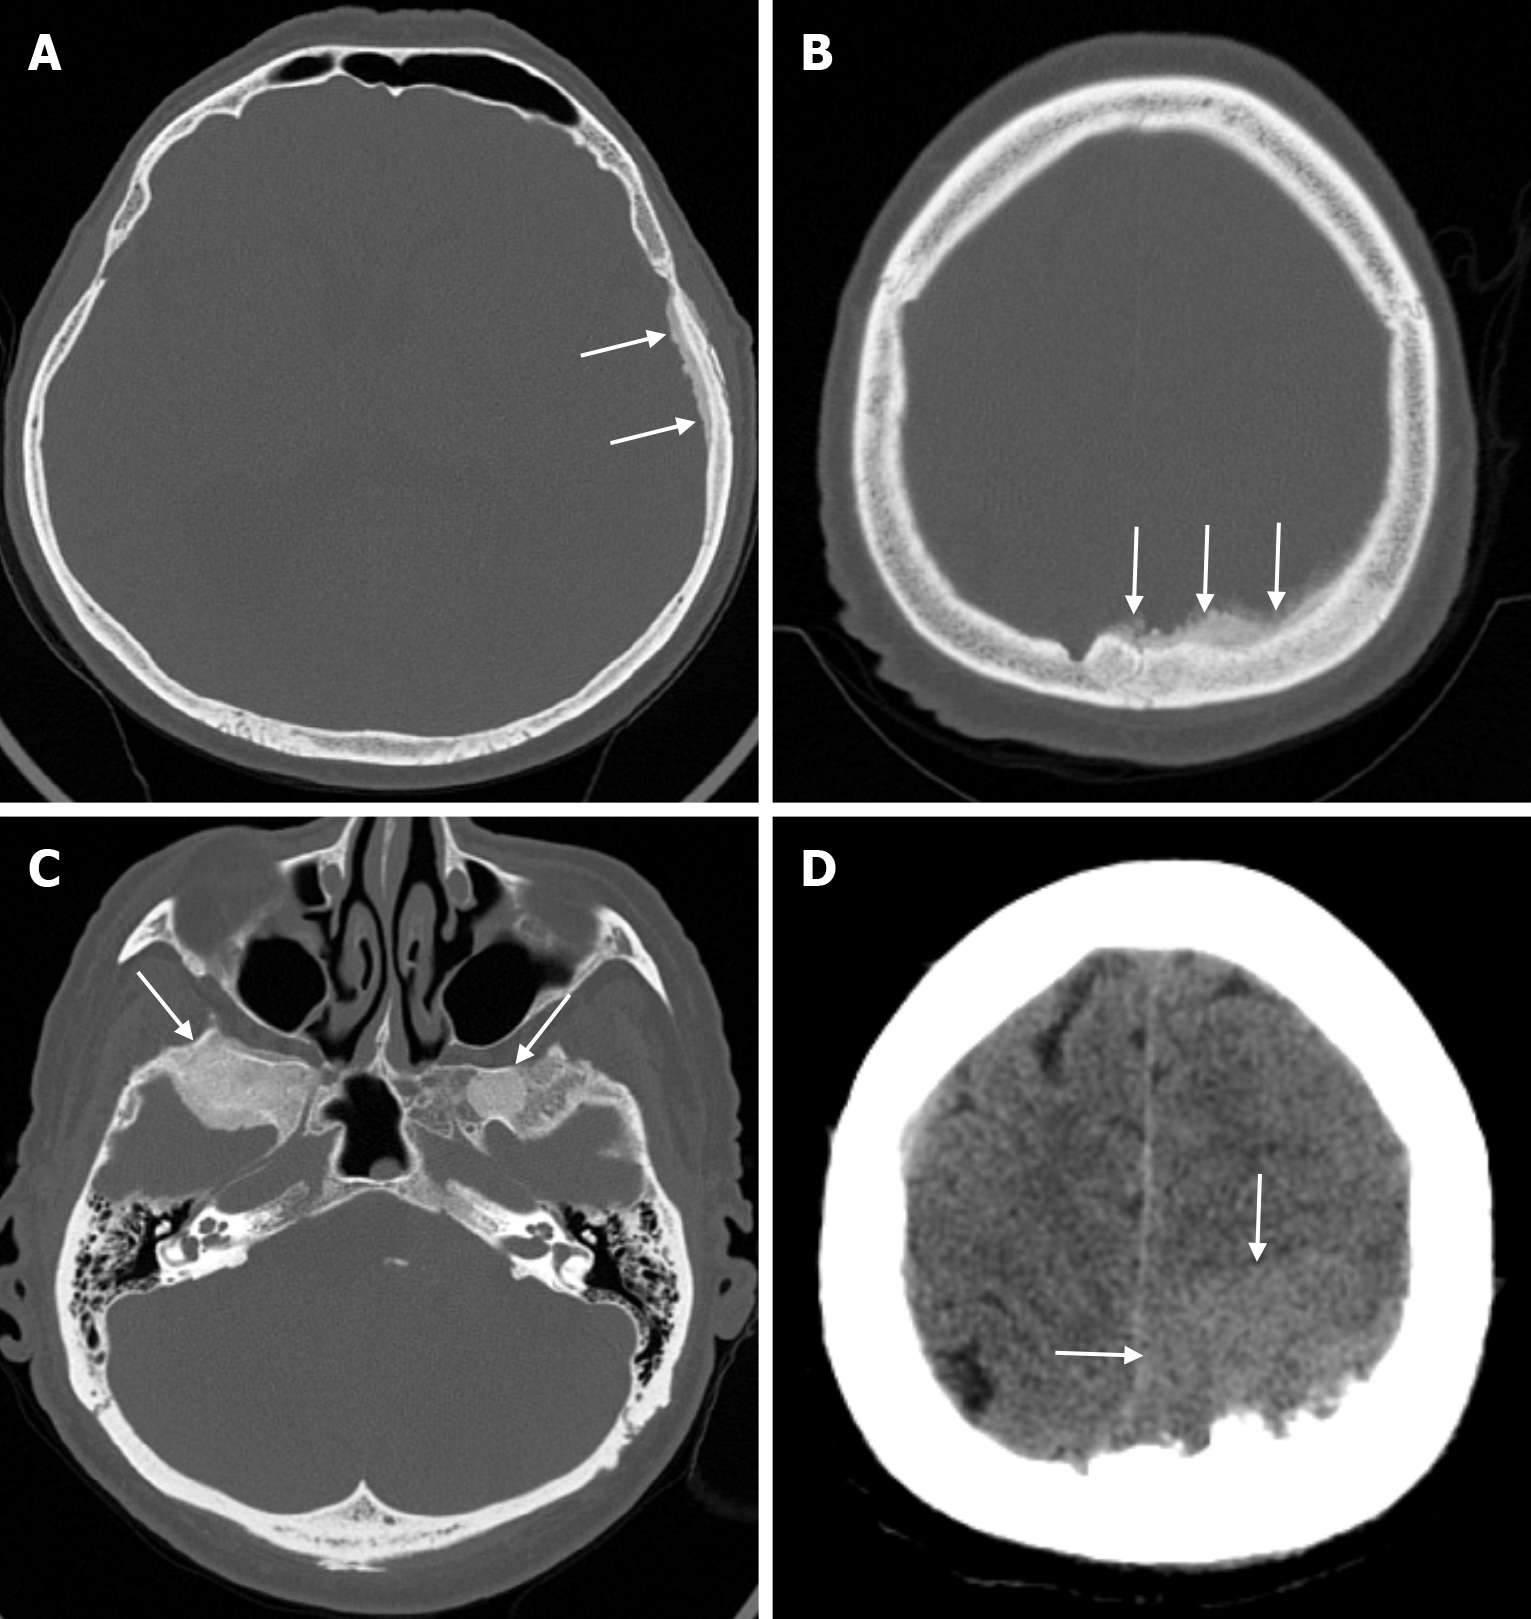

The beaten copper skull shows prominent convolutional markings on several bones of the skull. These convolutional markings normally appear between the ages of 2-3 and 5-7 years, which are periods of rapid brain growth. The occurrence of convolutional markings in children younger than 18 months should suggest a cause leading to increased intracranial pressure due to processes such as obstructive hydrocephalus, craniosynostosis or intracranial masses. Beaten copper skull pattern develops because of pressure applied to the soft skull by the growing brain. The beaten copper skull is usually confined to the posterior part of the inner table of the skull, but this appearance can affect the entire skull. Plain radiography of the skull can be an important diagnostic tool to detect increased intracranial pressure. In children, CT and three-dimensional reconstructions are best used to evaluate the convolutional markings (Figure 5) and cerebral ridges for surgical planning[23].

The prevalence of cranial osteomyelitis is 1.5% of all osteomyelitis cases, with a mortality rate of 20%-40%[45]. In developed countries, postoperative craniotomy infections are the most common cause of osteomyelitis, whereas in developing countries, sinusitis and scalp infections are the most common causes. It may occur as a complication of hematogenous spread or trauma. CT findings in the acute phase of osteomyelitis include areas of rarefaction and loss of diploic bone trabeculae; demineralization, erosion or thinning of the cortical bone table; and extracranial and subperiosteal abscesses. Diploic bone sclerosis and cortical bone thickening, radiolucent areas, and cortical disruption may occur in the chronic phase. Sequestration occurs as a result of the destruction of the skull base. On MRI may reveal an intracranial extension, particularly an epidural abscess and/or a subdural empyema. MRI findings in the acute phase of osteomyelitis include inflammatory replacement of diploic bone fat, widening of the diploic space, thinning of the skull base, increased signal intensity on T2-weighted images and contrast enhancement on T1-weighted images (Figure 12). In the chronic phase, sequestration, contrast enhancement in soft tissues and dura, and destruction of cortical bone fragments are seen. Bone scans using technetium-99m, gallium-67 citrate, single-photon emission computed tomography (SPECT), PET or PET-CT scans with 18F-fluorodeoxyglucose are highly effective in detecting cranial bone infections[46].

CT facilitates the diagnosis of pagetic abnormalities in bone that resemble findings seen on plain radiography. Because CT provides superior cortical and trabecular detail in a cross-sectional view, it better demonstrates osteolysis, trabecular coarsening, cortical thickening, and osseous expansion (Figure 13). In addition, CT often helps to assess complications such as fractures, spinal stenosis and secondary neoplasms.